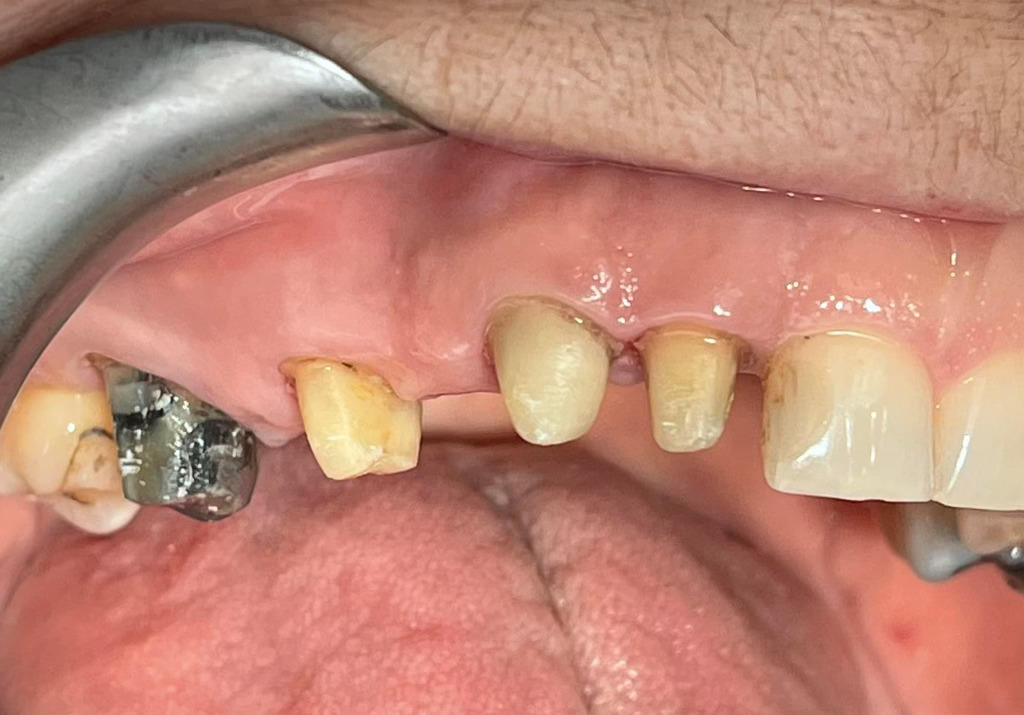

Case Study: Dental Bridges

Generate some text here.